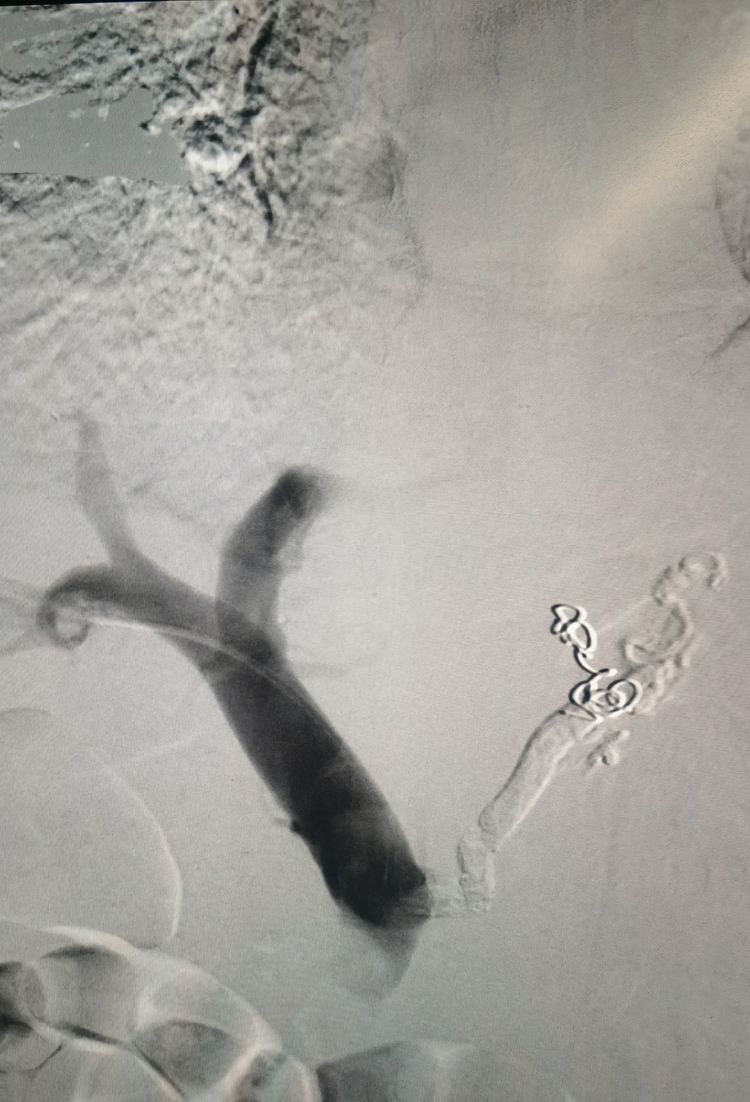

栓塞结束后再次造影:食管胃底曲张静脉消失。术后患者未出现呕血、黑便。

血管介入科刘顺帆主任介绍:PTVE是经皮肤肝脏穿刺至肝内门静脉分支,选择性的进行胃冠状静脉插管,用栓塞材料栓塞食管胃底曲张静脉,达到治疗食管胃底曲张静脉出血的一种有效的介入性治疗方法。临床研究证实PTVE在治疗食管胃底静脉曲张出血,降低病死率等方面有明显疗效。